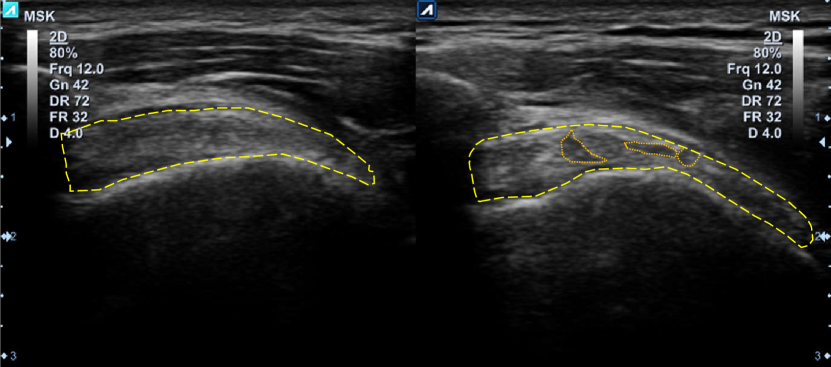

However, considering the common situations that patients are afflicted with tendon injuries and costs of MRI, it is always preferred to use a real-time, mobile, and cost-efficient modality like ultrasound (US) imaging [5]. Furthermore, recent studies confirmed that US imaging could be considered as a trustworthy replacement for MRI in the detection of tendinopathies [3, 5, 6, 7]. Nonetheless, US imaging modality has its drawbacks. For example, US images show less resolution and details for soft tissues while carrying more noise, i.e., having a lower signal to noise ratio (SNR) in comparison with MR images [8]. US images of SST for both left and right rotator cuffs of a person are depicted in Fig. 1(b). The left image of Fig. 1(b) corresponds to a normal SST, while the right image shows a tendinopathy case. Unlike MRI, injured regions of the tendon would appear darker than the healthy tissue in US imaging due to water/fat accumulation [5]. Also, the geometry of the abnormal case is changed especially in the peripheral region where tendon boundary is not smooth anymore, and it has become thinner in comparison to the normal case [5]. However, textural changes caused by tendinopathy in US images are not as apparent as they are in MR images. As Fig. 1(b) illustrates, texture differences between the normal and tendinopathy cases are very subtle and hard to detect (visual markers related to tendinopathy are annotated with orange dotted lines in Fig. 1(b)).

Figure 1: (a) illustrates the anterior view of the shoulder anatomy, showing brachii (BT), subscapularis (ST), and supraspinatus (SST) tendons (Image courtesy of Carolyn Nowak, Ann Arbor, Mich.), and (b) depicts the modified coronal view of the SST in US images of a normal case (left) and a tendinopathy case (right). The SST area is annotated with yellow dashed lines, and orange dotted lines indicate areas of tendon pathology.